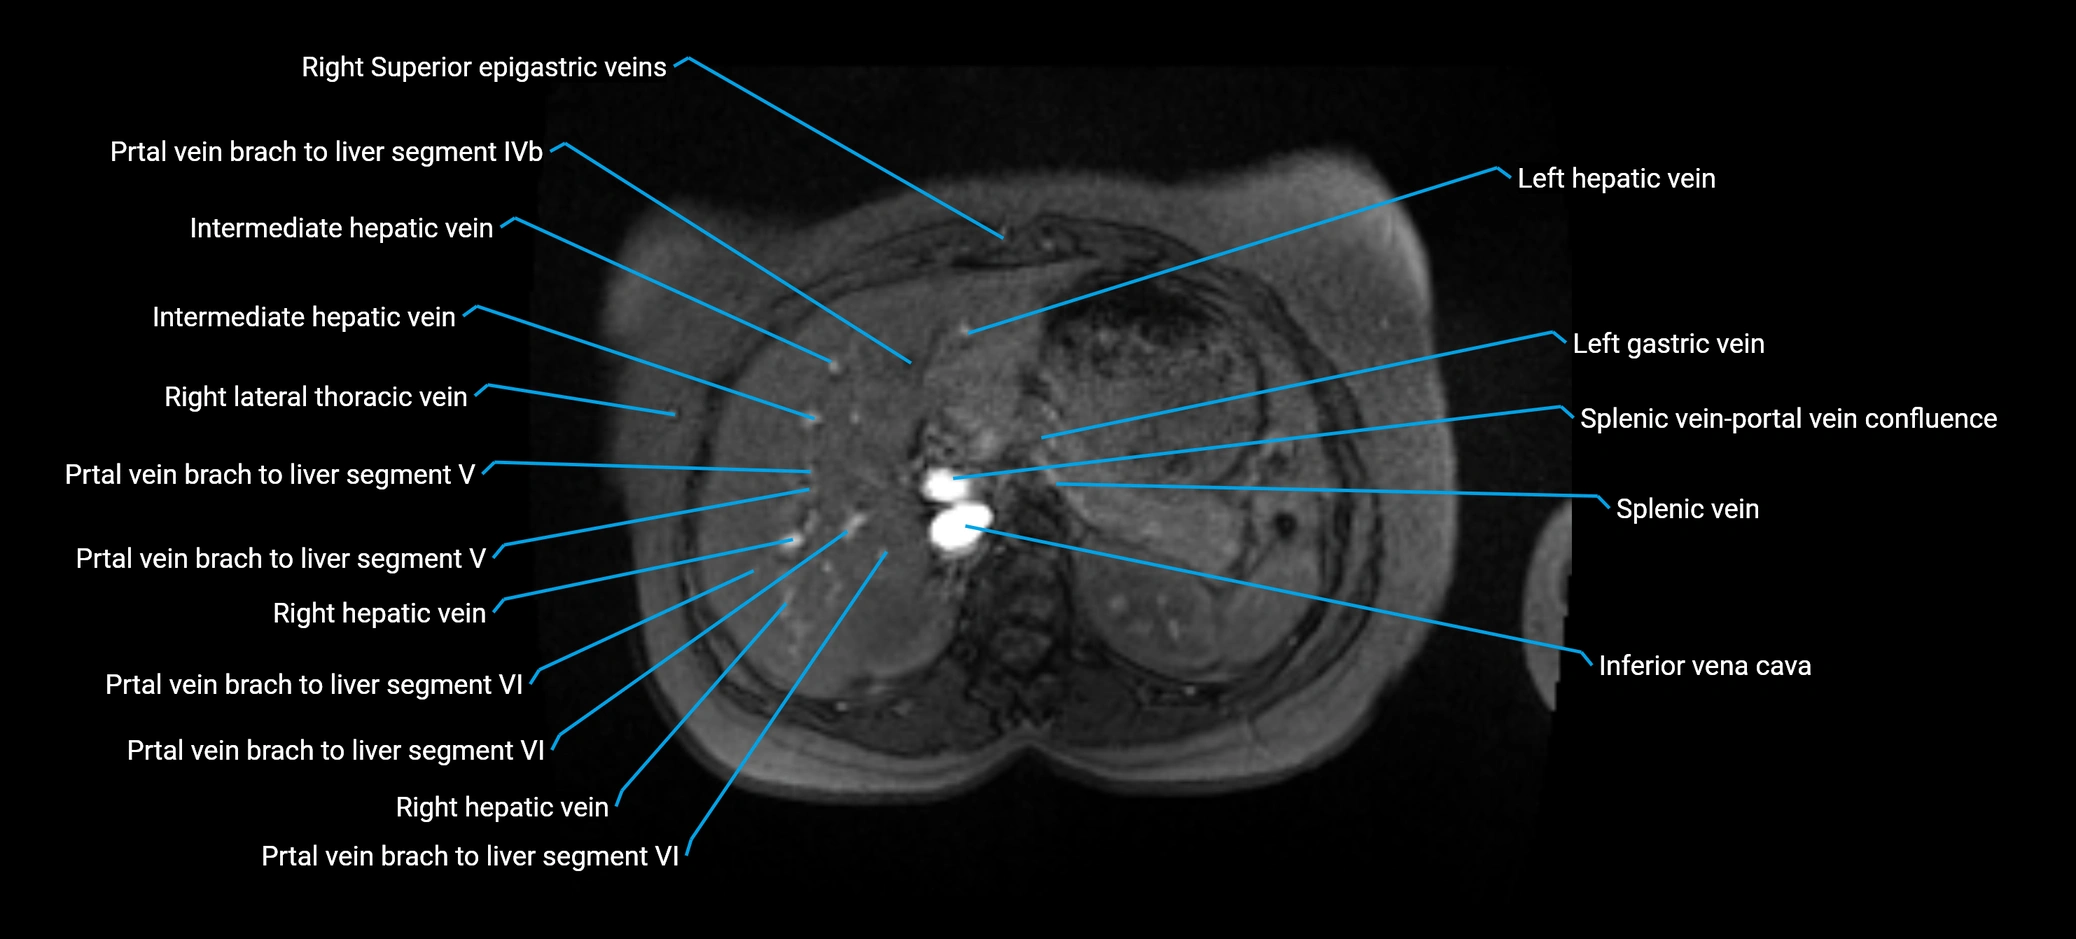

MRV TOF (Time-of-Flight MR Venography):

• Appears as a bright, high-signal vascular channel representing flowing blood

• Clearly shows branching pattern of right portal vein into anterior and posterior branches

• Best in coronal or axial reconstructions for segmental mapping

• No need for contrast, relies on flow-related enhancement

Post-Contrast T1 Fat-Sat GRE:

• Enhances brightly and homogeneously during the portal venous phase

• Clearly delineates branching into segments V and VIII

• Best sequence for evaluating patency, caliber, and anatomic variants

• Early arterial phase: minimal enhancement

• Delayed phase: gradual washout but still brighter than hepatic parenchyma

MRI image

image